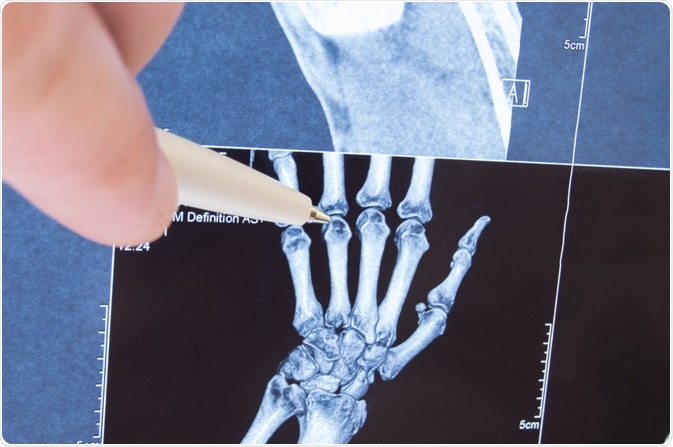

juvenile arthritisImage Credit: Shidlovski/Shutterstock.com